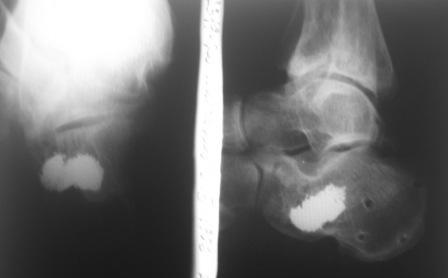

Из личного опыта могу сказать, что всё что в данном случае консервативно или минимизировано, закончится инвалидизацией и негативным отношением пациента к Вам. Можно закрыто выполнить репозицию, но как только, даже в отдалённый период(через 8 месяцев и более)начнётся полноценная нагрузка на конечность кость начнёт проседать со всеми вытекающими.

В качестве примера у себя нашёл снимки больного оперированного около двух лет назад, функция восстановлена полностью, ходит без каких бы то нибыло нарушений, сварщик - работает в полном объёме. Не сохранился первичный снимок, можете поверить на слово перелом примерно аналогичный, как у Вашего пациента.

Сделали данному больному операцию. Фиксация перелома спицами. Это интраоперационный снимок.